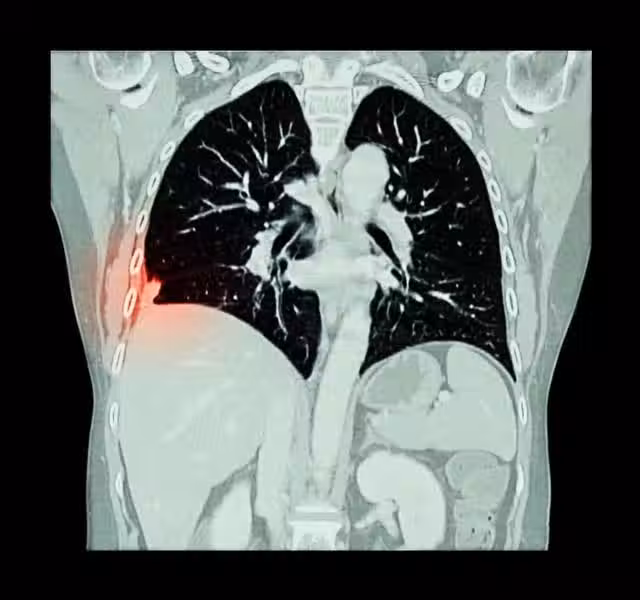

肺癌是一種嚴重的惡性腫瘤,它源自肺部組織的不受控制的細胞生長。隨著現代生活方式的變化和環境污染的加劇,肺癌的發病率逐年上升,給全球衛生帶來巨大的挑戰。雖然早期肺癌可能沒有明顯症狀,但當腫瘤逐漸增大或擴散時,患者的身體會出現一系列變化。

1、呼吸系統的變化:肺癌最常見於肺部的上皮組織,也可由其他部位的癌細胞轉移而來。肺癌的生長過程可以分為早期、局部進展和晚期擴散三個階段。在早期階段,肺癌可能沒有明顯的症狀,使其難以及時發現。隨著腫瘤的生長和擴散,患者的身體會逐漸出現呼吸系統的變化。